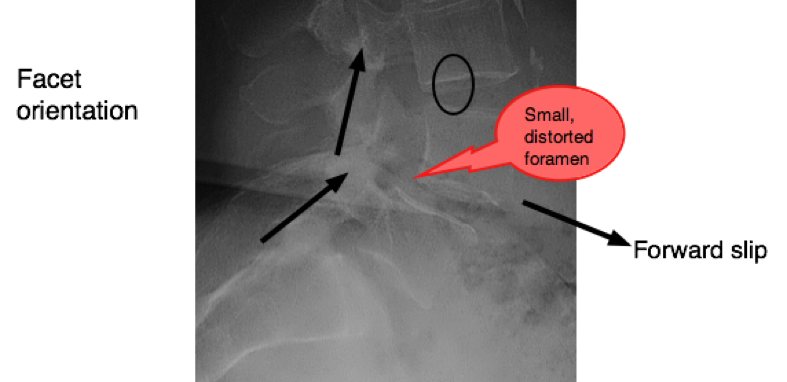

Each vertebra has two inferior facets that articulate with the two superior facets of the vertebra below it. Notice the locking mechanism: the inferior facet of the vertebra above locks onto the superior facet of the vertebra below preventing any possibility of a forward slip. Unless...

Worse is the second type, which is what this case file is about. The degenerative spondy, encountered in the older person, and quite unrelated to the Type I pars fracture type, is rarely stable.

Two things to notice in the diagram: